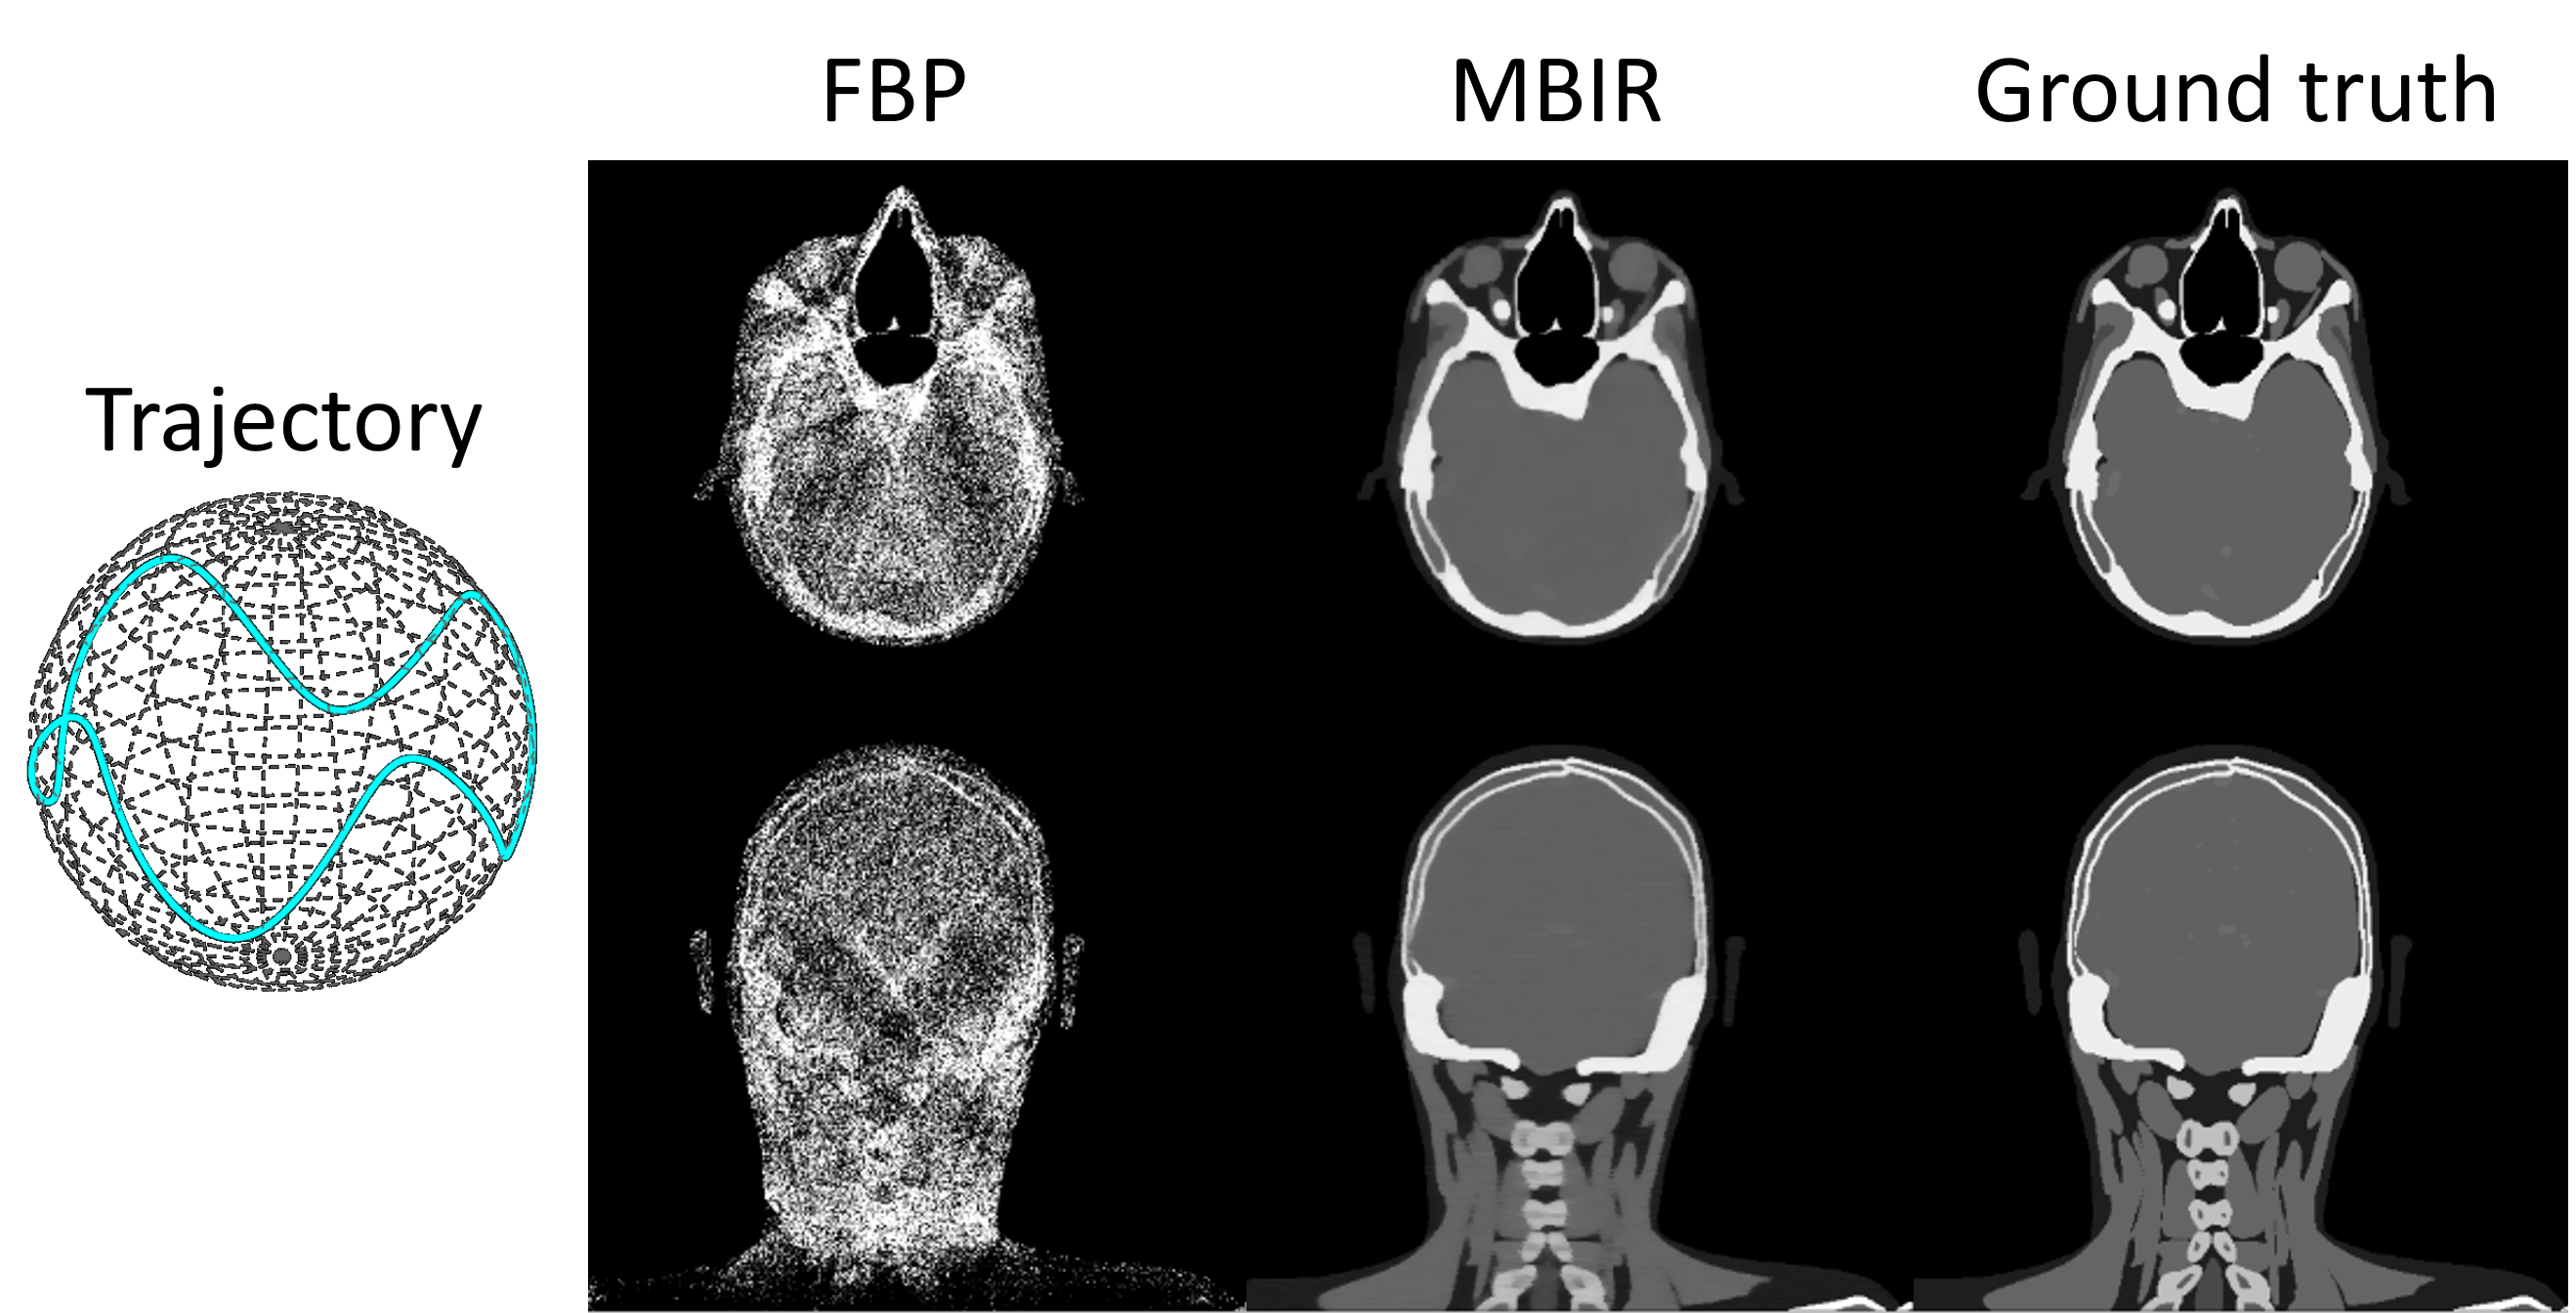

Finally, we validate the effectiveness of auto-differentiation through MBIR. As illustrated in Fig. 7, 200 head[segars20104d] cone-beam projections are simulated with a sinusoidal scan trajectory. The objective function of MBIR is formulated as:

x=argminxAxy22+λxTV\textbf{x}^{*}=\text{argmin}_{\textbf{x}}\|\textbf{Ax}-\textbf{y}\|_{2}^{2}+\lambda\|\textbf{x}\|_{TV} (3)

The objective function is minimized with 200 iterations of the Adam optimizer where the gradient is computed via auto-differentiation (as shown in the Sec.2.4). Due to the irregular projection sampling pattern, FBP reconstruction exhibits substantial non-uniformity. In contrast, MBIR effectively improves the reconstruction accuracy, as evidenced by a clear depiction of bone and soft tissue boundaries. These results validate the effectiveness of auto-differentiation in conjunction with the CTorch projector.

Figure 7: FBP and MBIR reconstruction of projections simulated with a non-circular scan trajectory.